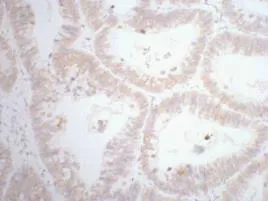

CDX2(14H6)Mouse Monoclonal Antibody

Cat: AMM08595

Size1:50μL Price1:$118

Size2:100μL Price2:$220

Size3:200μL Price3:$380

Application:WB,IF-P,IF-F,ICC/IF,IHC-P

Reactivity:Human,Mouse,Rat

Conjugate:Unconjugated

Optional conjugates: Biotin, FITC (free of charge). See other 26 conjugates.

Gene Name:CDX2